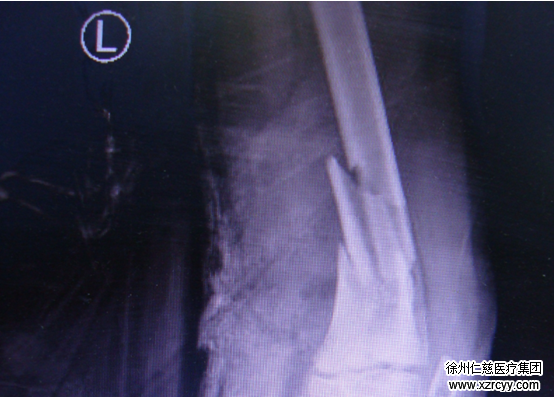

图一:术前检查

“你看这个图”黎医生指着伤口的照片(图二)说“股骨下端粉碎性骨折累及骨骺,腘动脉及伴行静脉完全栓塞,长约3cm,腓总神经、胫神经各断裂约1/4,股二头肌长头、腓肠肌、半腱肌、腘肌、跖肌各断裂约1/3。”从血肉模糊的照片中,很直观便能看到当时的严重程度。